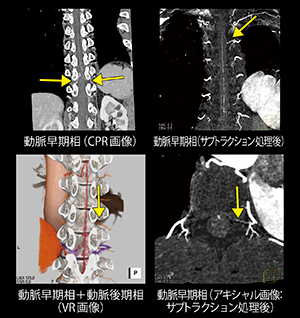

70kV Dual Powerを用いた脊髄動静脈瘻の描出

谷 和紀子(神戸大学医学部附属病院医療技術部放射線部門)

【背 景】67歳,男性。2014年9月頃から両下肢(右>左)の筋力低下が徐々に増悪し,転倒を繰り返すようになり,翌年5月,当院神経内科を紹介受診。腰仙椎MRIにてTh10レベルで脊柱管内に造影効果を伴う結節と,それから連続するような脊髄動静脈瘻様の管状構造物が認められたため,脊髄動静脈瘻の鑑別目的に胸腹部造影CTが依頼された。

【所 見】動脈早期相では,Th10レベルを中心に拡張蛇行する静脈の描出を認め,脊髄動静脈瘻であると考えられる。動脈後期相では,拡張した脈管はかなり強く造影されており,ここから連続してTh10の両側椎間孔へ向かう脈管が明瞭に描出され,流出静脈と考える。流入動脈は左Th10を疑う。アダムキュービッツ動脈は第7肋間動脈から分岐している。

【訴求ポイント】脊柱管内の細い血管を描出する際には,高線量での撮影および高レートでの造影剤注入が必要となる。動脈と静脈の分離が重要な脊髄動静脈瘻においては,複数時相の撮影が必要となり,被ばくの観点からも侵襲度が高い検査となる。本検査のポイントは,(1) 低電圧撮影により可能な限り造影剤のCT値を上げる:k-Edge近傍の70kVで撮影。(2) 低電圧撮影でも可能な限り画像ノイズの増加を抑える:2管球を用いてそれぞれから線量を与え(DSXXLモード),ピッチを小さくすることで十分な出力が可能となった。一方,頸椎から仙椎まで広範囲の動脈早期相および動脈後期相の2相撮影でも,70kVを使用することにより16.2 mGyと,胸腹部診断参考レベル以下の線量となった。(3) 再構成時にBeam Hardning Correction(BHC)およびADMIREを使用する:脊柱管内であっても高CNRを維持し,アーチファクトも少ない画像を得ることができた。